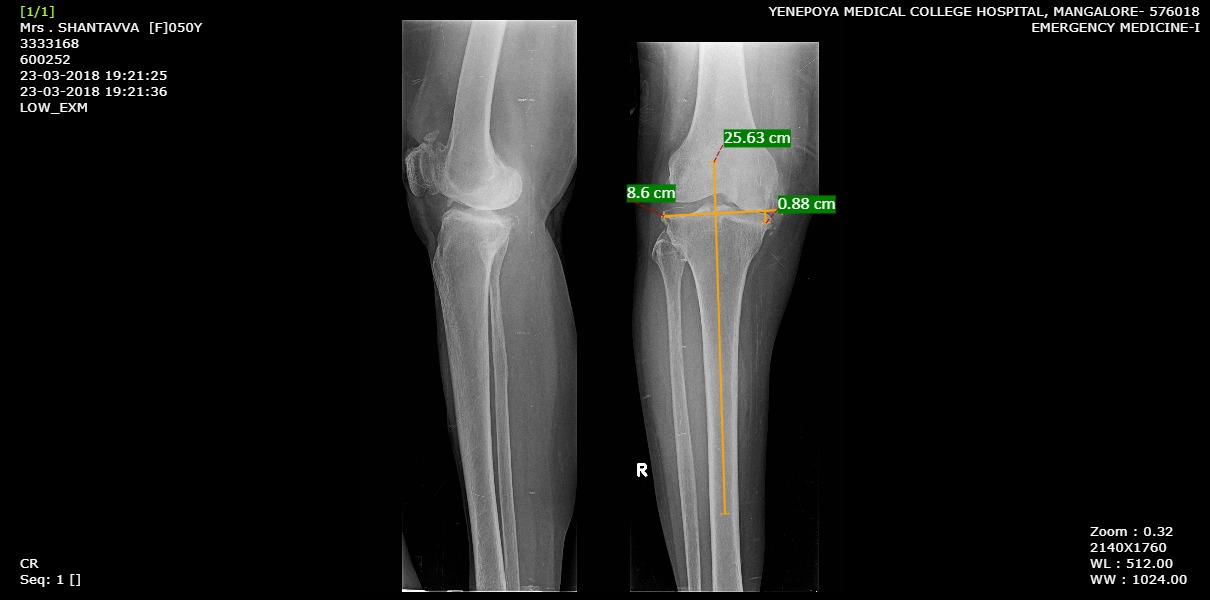

Assessment of radiographs

Standard Antero-posterior and Lateral view weight bearing radiographs of the knee were taken. The bone loss was calculated as the bone defect in mm at the medial tibial plateau when a line is drawn from the lateral tibial plateau perpendicular to the long axis of the tibia. All films were assessed in a blinded manner. The Ahlbäck and Rydberg [7] grading was applied to assess the severity of bone loss where Grade 1: narrowing of the articular space; Grade 2: obliteration of the articular space; Grade 3: bone attrition less than 5 mm; Grade 4: bone attrition between 5 and 15 mm, and Grade 5: bone attrition greater than 15 mm.